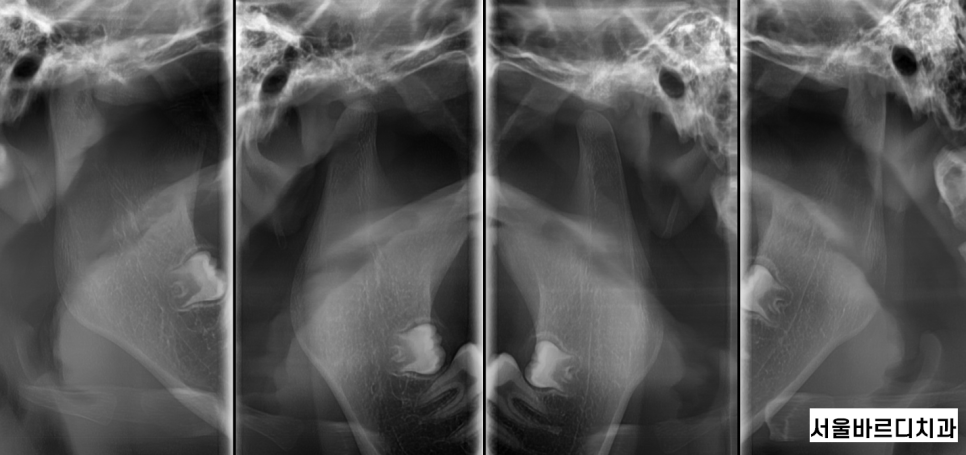

- 턱관절 장애

치아 교정과 턱관절이 무슨 상관이에요? 싶으시겠지만..

치아 교정 과정에서

턱의 위치가 변하면서 턱관절에 무리가 가해질 수 있습니다.

이로 인해 턱에서 소리가 나거나

통증이 발생할 수 있으며,

심한 경우 입을 벌리거나 닫는 것이

어려워질 수도 있습니다.

상일동역 치아교정 전에 턱관절 상태를 면밀히 검사하고

교정 중에 불편함이 느껴지면 턱 치료를 병행하고 있답니다!!